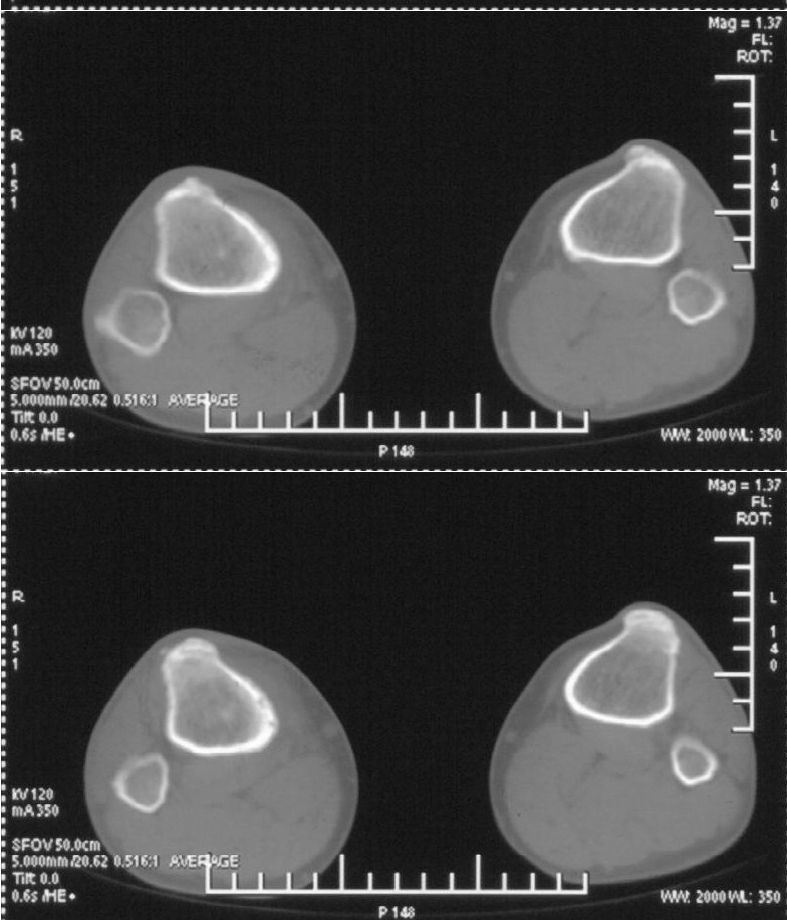

男,42岁。4个月前钢筋钝伤右侧小腿部,当时因无明显外伤,未引起重视。一周后因受伤腿部疼痛,发现肿胀,随后到当地医院进行检查(2008年4月16日)。因未发现骨质异常未引起重视,仅仅进行口服抗生素治疗处理。经过一段时间治疗但未见明显治疗效果在5月29日又进行x线检查,发现有胫骨密度上段密度增高,又进行抗炎治疗,仍未见效果。又在7月3日进行x线检查,仍然报告有胫骨上端密度增高,并建议ct检查。以下是相关检查结果:

髓腔密度呈絮状增高,胫骨上端内侧可见层状骨膜反应,考虑骨髓炎.

髓腔密度呈絮状增高,胫骨上端内侧可见层状骨膜反应,肌间隙模糊,考虑骨髓炎.

破坏、增生、骨膜反应,考虑骨髓炎